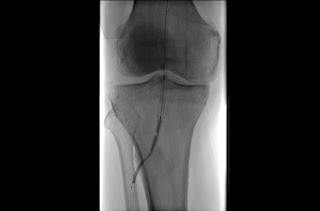

4. Angiography

This is a special type of X-ray technique for viewing blood vessels and organs, especially the heart, by injecting a contrast agent into the blood that enhances its visibility on the X-ray image.

figure 8: Angiography of a blood vessel in the region of the knee